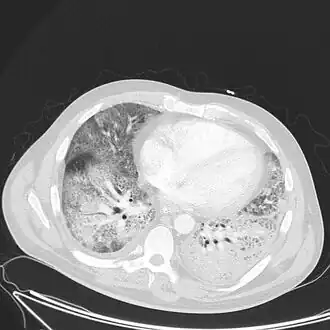

Medical imaging

Radiologic imaging has long been a criterion for diagnosis of ARDS. Original definitions of ARDS specified that correlative chest X-ray findings were required for diagnosis, the diagnostic criteria have been expanded over time to accept CT and ultrasound findings as equally contributory. Generally, radiographic findings of fluid accumulation (pulmonary edema) affecting both lungs and unrelated to increased cardiopulmonary vascular pressure (such as in heart failure) may be suggestive of ARDS. Ultrasound findings suggestive of ARDS include the following: